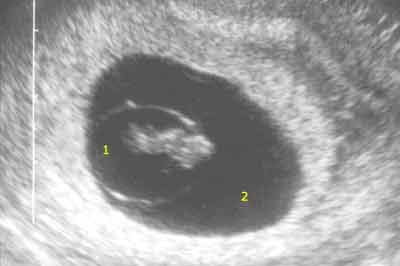

1- Cavité amniotique

2- Coelome extra embryonnaire